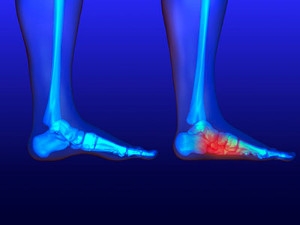

Causes of Heel Pain

Heel pain is common and there are several causes. It can occur as a result of an injury or from wearing shoes that do not have adequate cushioning in the heel area. The foot condition known as plantar fasciitis can cause severe heel pain and a podiatrist is often consulted for relief. Additionally, enduring an Achilles tendon injury can also produce heel pain, and it can become difficult to walk. People who are afflicted with arthritis in the feet may have swollen heels and a reduced range of motion. For moderate heel pain, performing gentle stretches can help to strengthen the heel and it is helpful to avoid wearing high heels. A heel spur is a bony growth that forms on the bottom of the heel that causes heel pain, too. A heel spur can be diagnosed by having an X-ray taken to determine its size. If you have heel pain, it is strongly suggested that you are under the care of a podiatrist who can analyze the cause and offer you the correct treatment solutions.

Causes of Heel Pain

Heel pain is often associated with plantar fasciitis. The plantar fascia is a band of tissues that extends along the bottom of the foot. A rip or tear in this ligament can cause inflammation of the tissue.

Achilles tendonitis is another cause of heel pain. Inflammation of the Achilles tendon will cause pain from fractures and muscle tearing. Lack of flexibility is also another symptom.

Heel spurs are another cause of pain. When the tissues of the plantar fascia undergo a great deal of stress, it can lead to ligament separation from the heel bone, causing heel spurs.